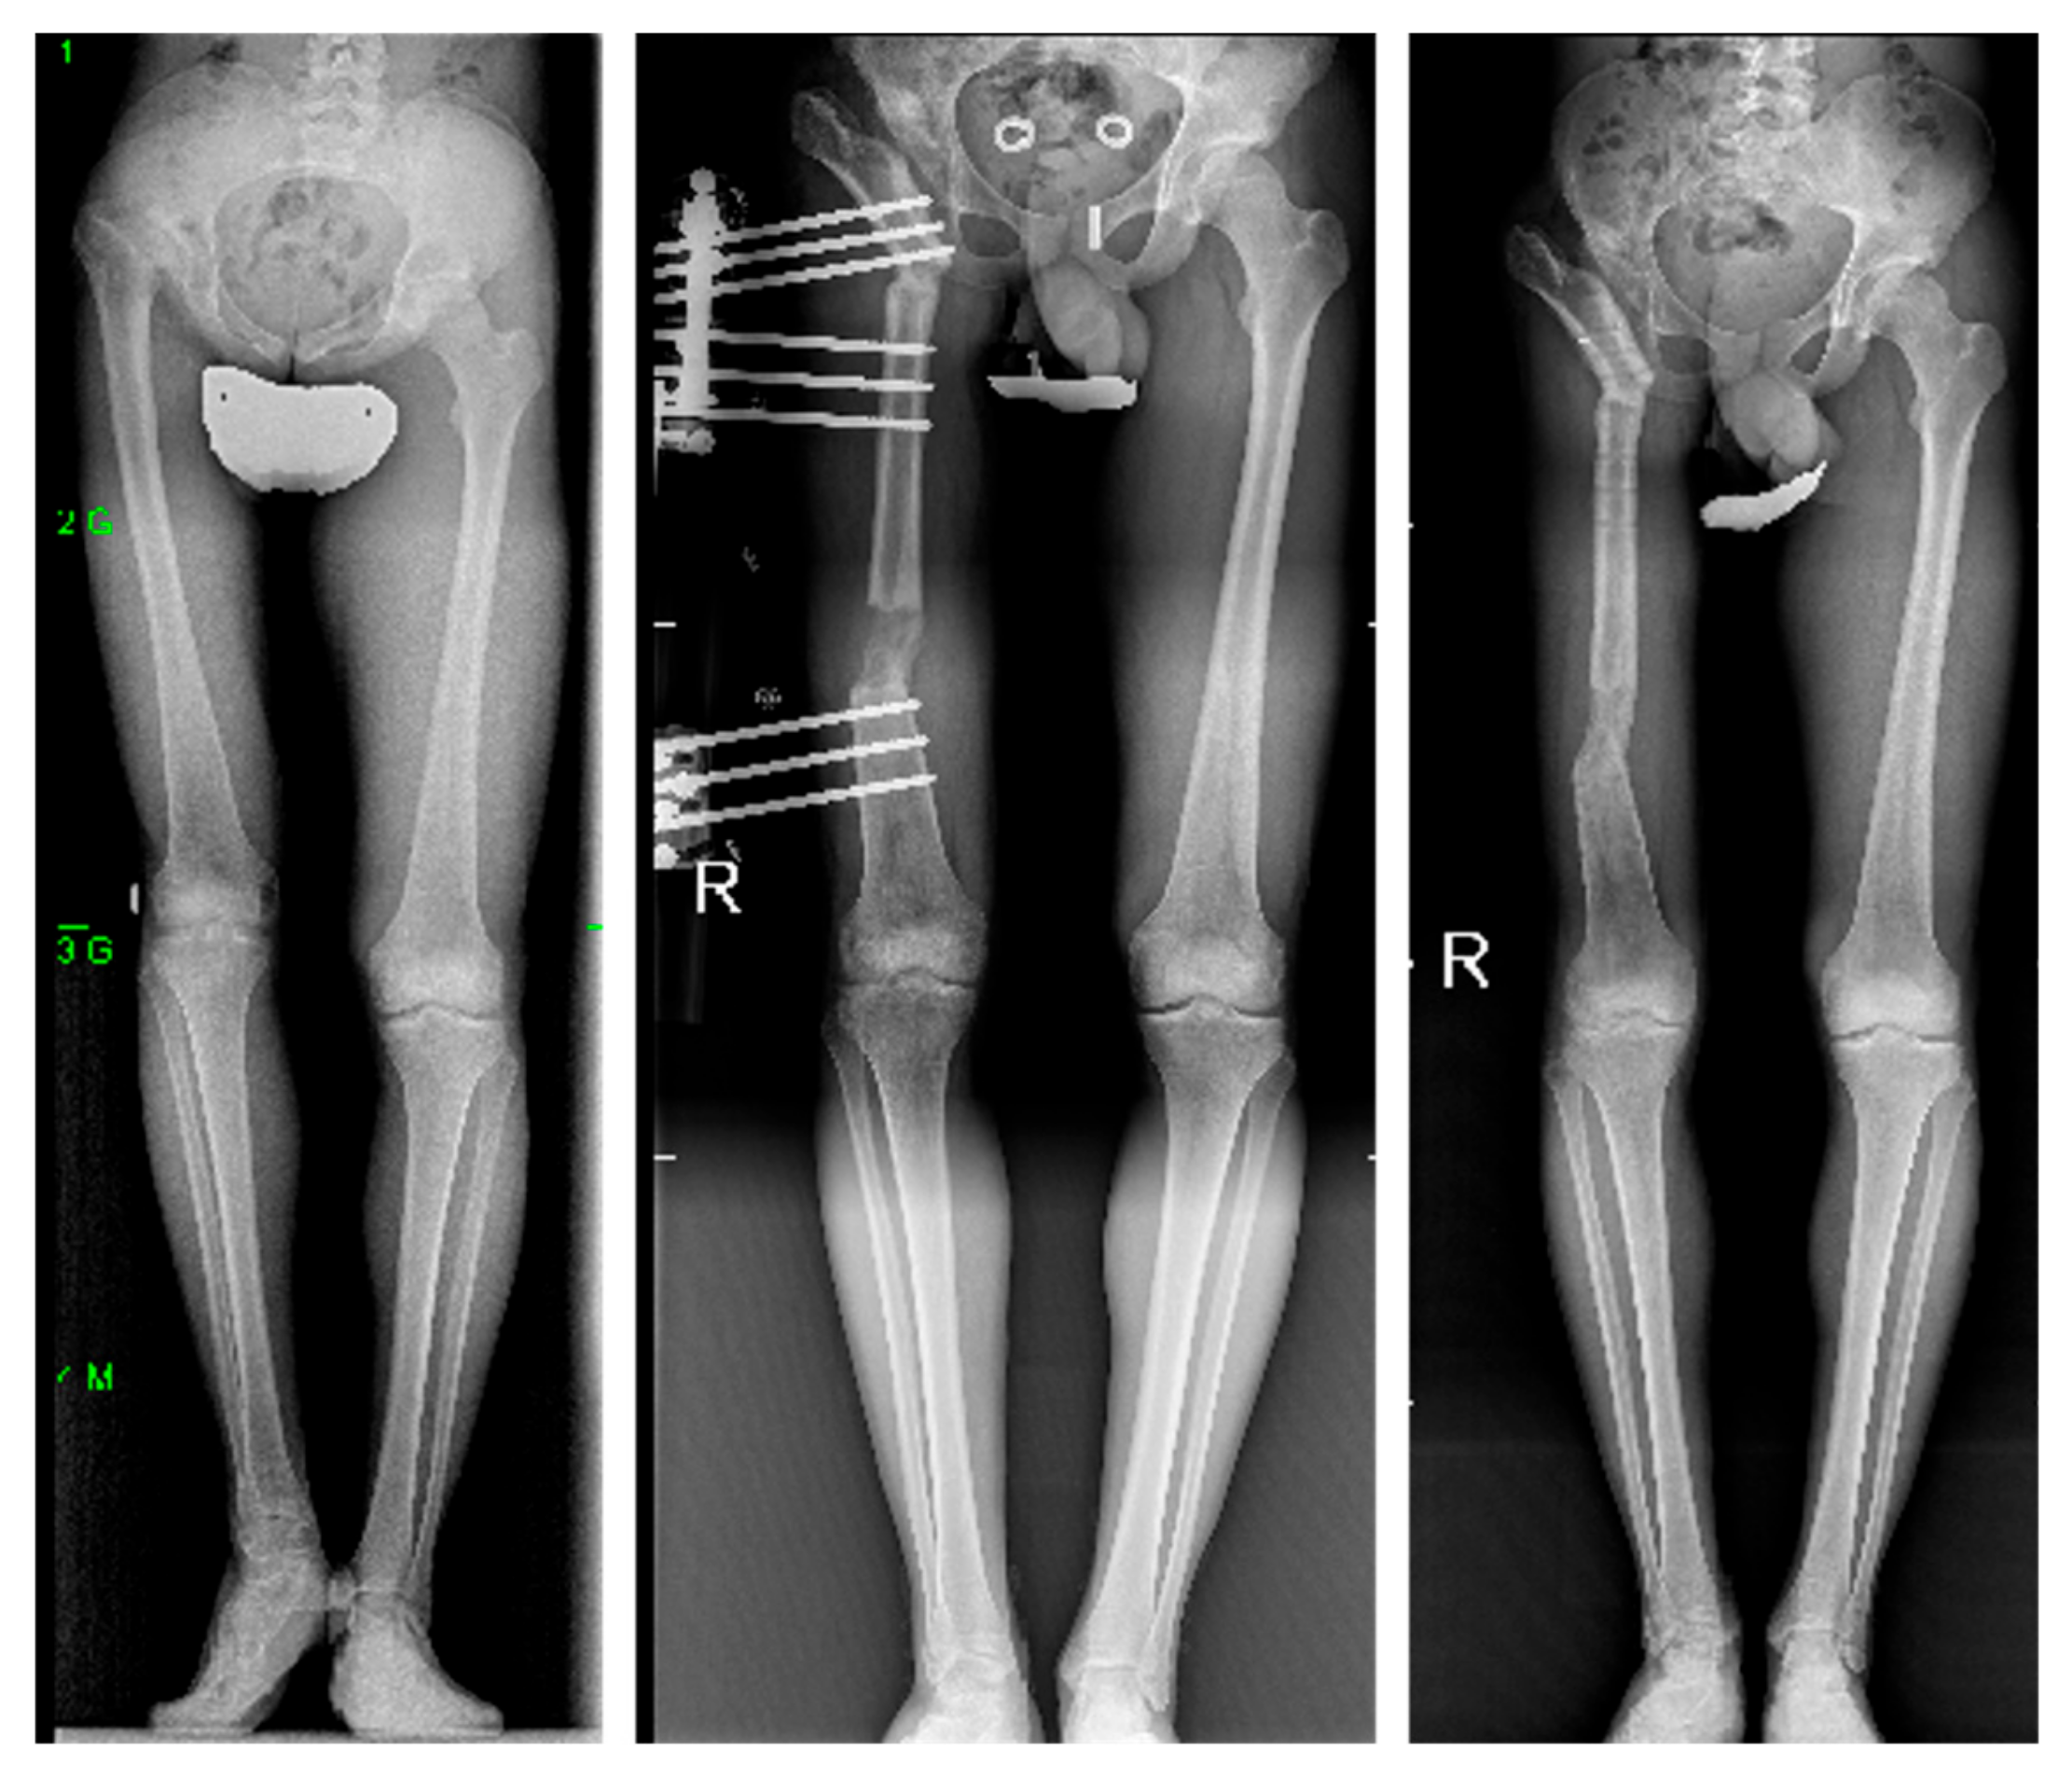

| Case | PreOp Leg Length Discrepancy (cm) | Lengthening (cm) | FollowUp Leg Length Discrepancy (cm) | ExFix Time (days) | ExFix Index (days/cm) | PreOp Trendelenburg | FollowUp Trendelenburg |

|---|---|---|---|---|---|---|---|

| 1 | 8 | 8 | 1 | 270 | 33.8 | Severe (+++) | Mild (+) |

| 2 | 7 | 7 | 2 | 210 | 30.0 | Severe (+++) | Negative (−) |

| 3 | 10 | 10 | 0 | 360 | 36.0 | Severe (+++) | Mild (+) |

| 4 | 10 | 10 | 2 | 320 | 32.0 | Severe (+++) | Moderate (++) |

| 5 | 5 | 5 | 0 | 180 | 36.0 | Severe (+++) | Negative (−) |

| 6 | 7 | 7 | 2 | 210 | 30.0 | Severe (+++) | Mild (+) |

| 7 | 10 | 10 | 0 | 330 | 33.0 | Severe (+++) | Mild (+) |

| 8 | 9 | 9 | 3 | 225 | 25.0 | Severe (+++) | Mild (+) |

| 9 | 9 | 9 | 0 | 330 | 36.7 | Severe (+++) | Mild (+) |

| 10 | 7 | 7 | 1 | 240 | 34.3 | Severe (+++) | Moderate (++) |

| 11 | 6 | 7 | 0 | 210 | 30.0 | Severe (+++) | Negative (−) |

| 12 | 8 | 8 | 0 | 270 | 33.8 | Severe (+++) | Mild (+) |

| Total | 8 | 8.1 | 0.9 | 263 | 32.6 | 12 +++ | 2 ++; 7 +; 3 − |